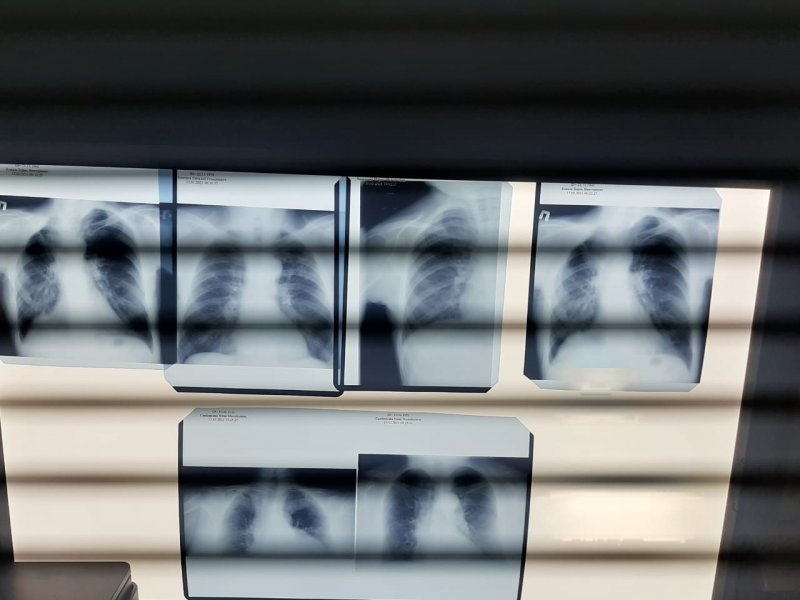

До 26 марта каждый желающий может без направления обратиться в противотуберкулезный диспансер и пройти флюорографическое исследование, спирографию, экспресс-тестирование на ВИЧ-инфекцию, получить консультацию детского или взрослого фтизиатра. Детям могут сделать манту или диаскинтест.

«Пациенты участвуют в этой акции очень активно. Я приехал на работу к 8 утра, и уже было много желающих пройти обследование. Севастопольцы достаточно активно и внимательно относятся к своему здоровью и пользуются возможностью проверить здоровье без записи к специалисту», — рассказал главный врач противотуберкулезного диспансера Андрей Вербицкий.

Противотуберкулезный диспансер работает с 8 до 18 часов. Детей принимают до 14 часов, взрослых и подростков — до конца рабочего дня. С собой необходим только документ, удостоверяющий личность.